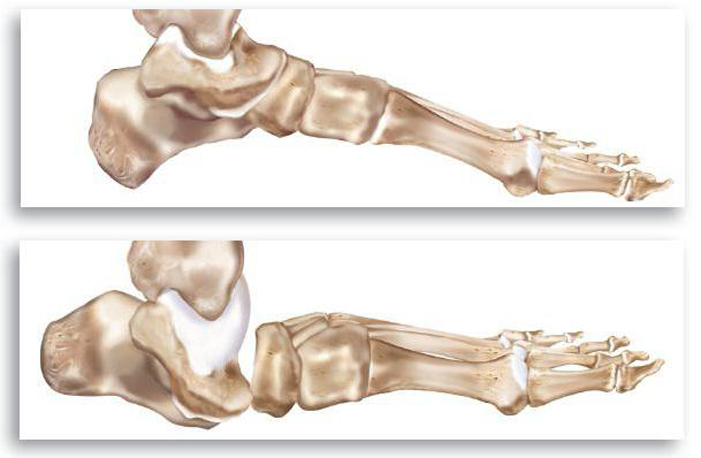

На подострой стадии отек поврежденной конечности усиливается. Рентгенограмма показывает деформацию костей стопы, в суставе появляется хруст и боль при движении.

Для второй стадии характерны заметные различия между здоровой и пораженной ногами, а также уплощение пострадавшей стопы.

На хронической стадии деформация стопы становится очевидной даже без специального оборудования. Происходит вальгусная деформация, при которой ось пятки искривляется и заваливается внутрь.

На стадии хронического протекания болезни рентгенография выявляет кальцификацию костей и снижение плотности костной ткани. Искривления наблюдаются в области фаланг пальцев, плюсны и предплюсны. Все пальцы на пораженной ноге поджаты, а переломы и вывихи могут происходить спонтанно, без физического усилия.

Для осложненной стадии болезни характерны деформации, присущие диабетической стопе. Кости, связки и мягкие ткани разрушаются, теряя свою функциональность. У пациентов развиваются трофические язвы, кожа на подошве утолщается и появляются болезненные трещины. Разрушение костей приводит к их фрагментации, что делает стопу похожей на мешок с костями на рентгеновском снимке.